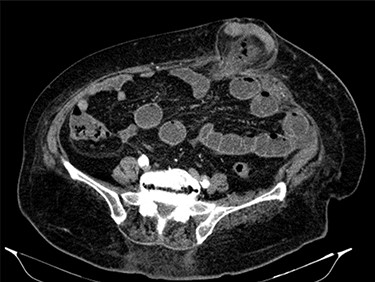

Fluid resuscitation measures, monitoring of urine output and pain control were initiated. Analytically, she had leukocytosis of 227 000/μl with neutrophilia 89%, elevated C-reactive protein 27.1 mg/dl and acute kidney injury with creatinine 1.8 mg/dl and urea 96 mg/dl. Arterial blood gas analysis showed no acidosis, respiratory failure or hyperlactatemia. The computed tomography (CT) scan identified an umbilical hernia containing a small bowel loop, evidenced densification of the hernia fat and some bubbles of extraluminal gas were also present (Fig. 2). An image of high-density and filiform morphology compatible with an FB (Fig. 3) was also identified. Images were consistent with dilation of the proximal intestinal loops, which suggested bowel occlusion.

Abdominal CT: hernia content composed of intestinal loop and densification of the mesentery with gas bubbles.